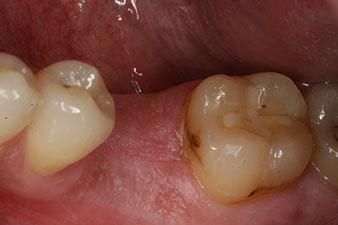

measuring probe

Fig. 6: Ten weeks later the gingiva former, which was screwed in place after placement of the implant, can be removed. In the linguo-buccal direction the ISQ value was virtually unchanged at 63 (measuring probe in proximity at a distance of 2-3 mm).

The implant was uncovered two months later and a gingiva former was screwed in (no picture).

After healing of the soft tissue, the implant stability was measured again before delivery of the prosthetic restoration.

Both values were virtually unchanged and were between the medium and the high range – where the lower value is always used as the reference value that determines the treatment.

Therefore, successful osseointegration and adequate biological stability could be recorded, which enabled an impression to be taken in the same session.